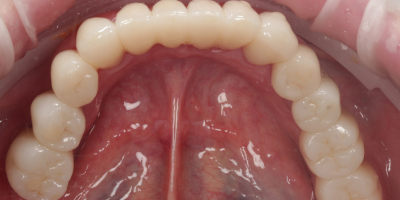

Была проведена имплантация: установлены импланты в области жевательных зубов нижней челюсти и в зоне переднего зуба верхней челюсти. После остеонтеграции имплантатов - проведено протезирование циркониевыми коронками.

Комплексное лечение позволило одновременно сохранить собственные зубы и восполнить отсутствующие участки с помощью имплантатов. Временные конструкции обеспечили адаптацию и комфорт сразу после операции. Постоянные циркониевые коронки восстановили гармонию улыбки, прочность и долговечность. В итоге пациент получил полноценный зубной ряд и красивую естественную улыбку.